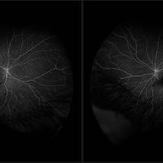

Background: 46-year-old WF with CML (stable on Sprycel) saw her PCP for headaches without known cause; Headaches worsened and became confused, disoriented, off balance, and impaired short term memory. Heme-oncology ordered MRI that showed abnormal signal in the cerebellum and other parts of the brain, and LP has elevated protein. LP did show positive tau test, but fortunately, was a false positive for CJD. IV and PO steroids started and symptoms improved. MRI showed much improvement one month since starting steroids. 3 weeks later had a scotoma in right eye and eye doctor did not find anything at that time to cause it. Tinnitus developed (and some intermittent vertigo before that) and ENT referred back to eye doctor, who then referred the patient to Dr. Zocchi. He found a CWS and superotemporal BRAO OD, and bilateral arteritis. She had some additional work-up for vasculitis. Given the retinal arteritis, cochlear issues, and MRI findings, Dr.Zocchi suspected Susac's Syndrome. She was started on multiple regimens including prednisone, IVIG, azathiprine, and MTX, and has had the best reponse to IVIG (this FA is one month post recurrence with resolved inferotemporal BRAO after prednisone taper and increase in IMT). She is stable and doing well with 20/20 vision in both eyes.

Photographer: Kay Dalby

Imaging device: Topcon

Condition/keywords: retinal vasculitis, Susac's syndrome